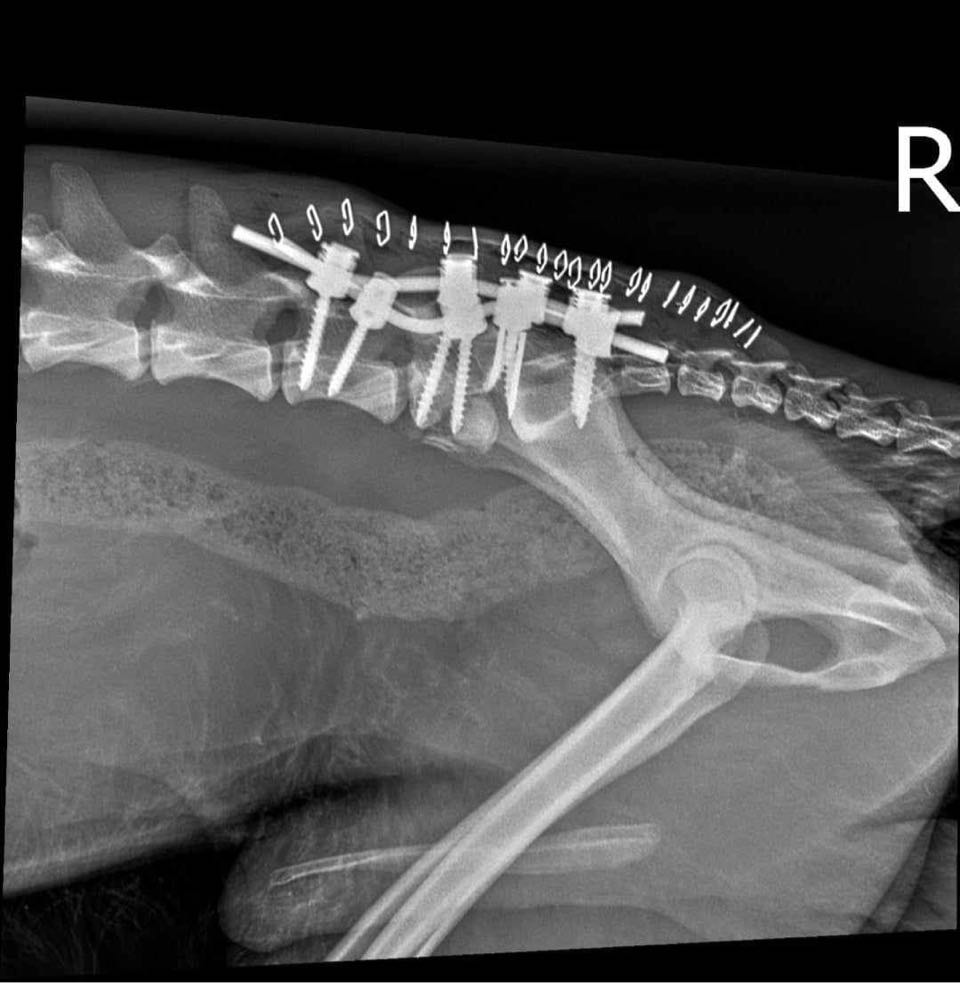

CIPRIAN konnte von unseren Tierschützern vor Ort gerettet werden. Er wurde im Februar 2024 bereits verletzt zwischen die Gleise einer Zugverbindung im Niemandsland gelegt. Aufgrund eines Hinweises konnte er dort geborgen werden und wurde bereits in einer Bukarester Fachklinik an der Wirbelsäule operiert. Inzwischen – Stand Anfang März 2024 – kann er bereits selbstständig wieder laufen, ist aber natürlich noch wackelig und mit kleinen Aussetzern unterwegs.

zur Besonderheit: hatte Wirbelsäulen-OP